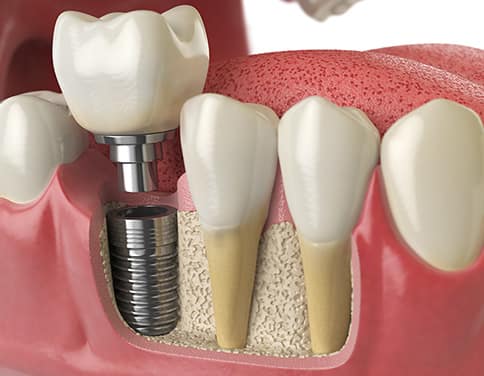

欠損部分をインプラントで治療し、下顎の歯をセラミックで審美的に改善したケース。